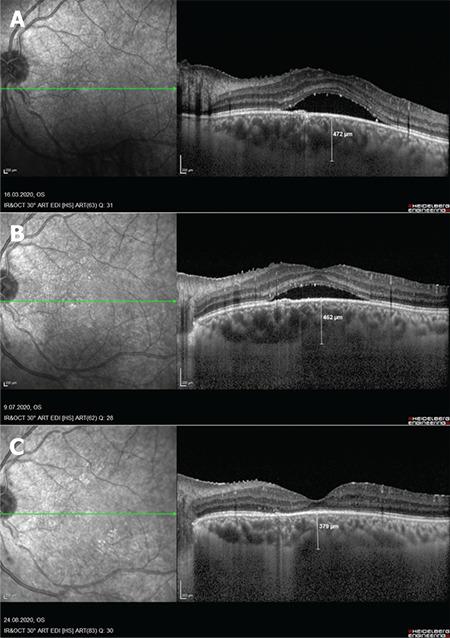

Corticosteroid-induced central serous chorioretinopathy (CSCR) has been reported to develop in many intraocular inflammatory diseases and usually resolves spontaneously after discontinuation of corticosteroids. Patients without any improvement may require alternative therapies. In this case report, we present the case of a 35-year-old man with Behçet's disease who had complaints of decreased vision due to CSCR in his left eye while using systemic corticosteroids along with cyclosporine and azathioprine. Half-fluence photodynamic therapy (PDT) was performed because the CSCR did not regress despite discontinuation of systemic corticosteroids. After treatment, his visual acuity increased with complete resolution of the subfoveal fluid. Half-fluence PDT seems to be an effective and safe treatment for patients who develop acute CSCR while under systemic or local corticosteroid therapy for intraocular inflammatory diseases such as Behçet's uveitis and do not improve despite steroid discontinuation.

皮质类固醇诱导的中心性浆液性脉络膜视网膜病变(CSCR)已在许多眼内炎症性疾病中报道,通常在停用皮质类固醇后会自发消退。没有任何改善的患者可能需要替代疗法。在本病例报告中,我们介绍了一名 35 岁男性的病例,他患有贝切特病,在使用环孢素和硫唑嘌呤的同时全身使用皮质类固醇,左眼出现 CSCR,视力下降。尽管停用全身皮质类固醇,但 CSCR 仍未消退,因此进行了半剂量光动力疗法(PDT)。治疗后,他的视力提高,黄斑下积液完全消退。对于在眼内炎症性疾病(如贝切特葡萄膜炎)中接受全身或局部皮质类固醇治疗时发生急性 CSCR 且尽管停用类固醇仍未改善的患者,半剂量 PDT 似乎是一种有效且安全的治疗方法。